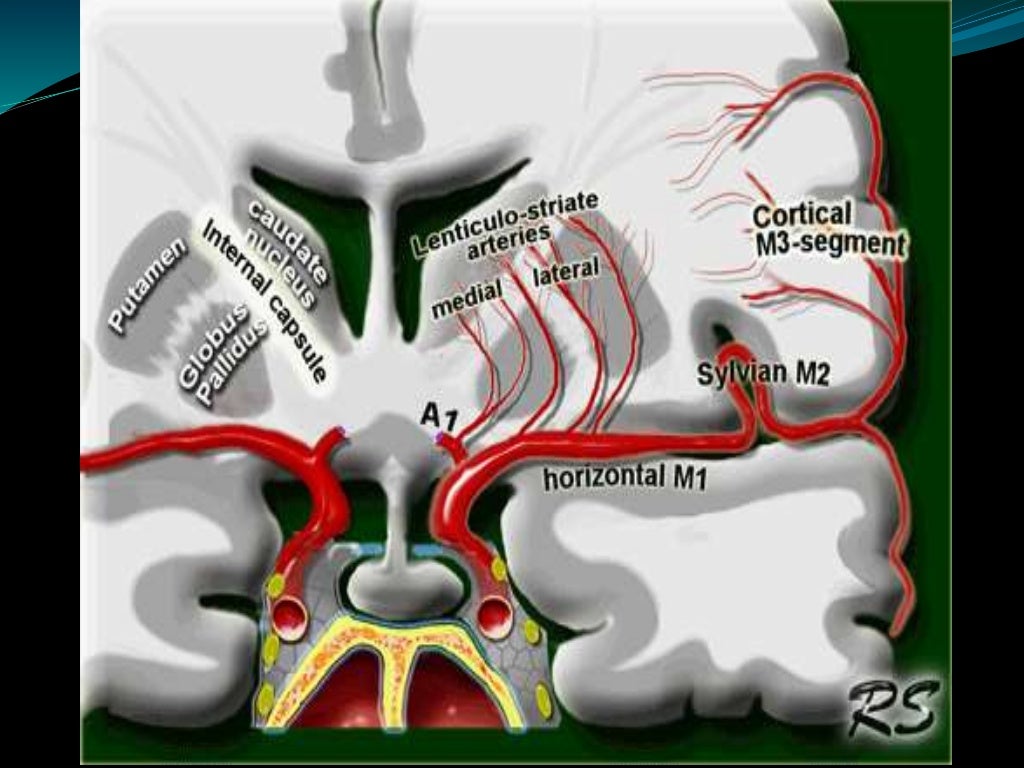

hemorragia cerebral Puede deberse a un trauma cerebral. The following 2 files are in this category, out of 2 total. Media in category intracerebral hemorrhage. La causa suele ser la hipertensión. Puede ser externo o dentro del cuerpo. Como ya se ha mencionado, suele estar relacionada con la hipertensión. Un hematoma intracraneal es una acumulación de sangre dentro del cráneo. En general, se distinguen entre hemorragias profundas (incluyendo aquellas que afectan a núcleos grises profundos de los hemisferios cerebrales), hemorragias.

Hemorragia Intracerebral subraquídea Neurocirugía de la Torre